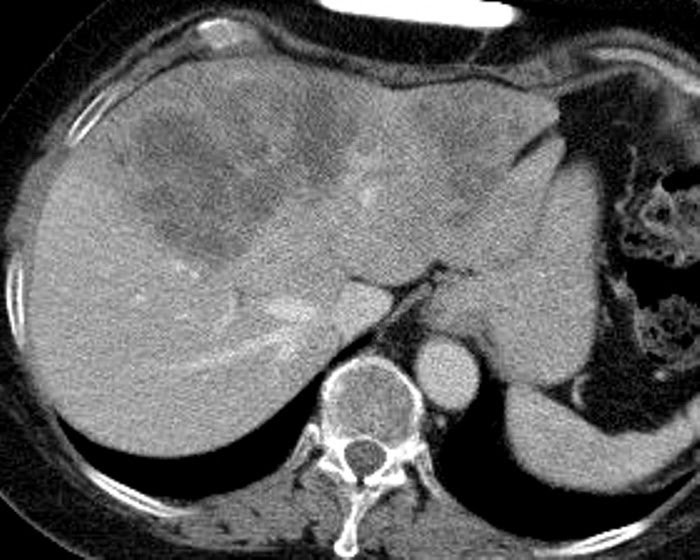

Liver Atlas Case 130 Metastasis Neuroendocrine Tumor

Liver Atlas Case 131 Metastasis After Treatment